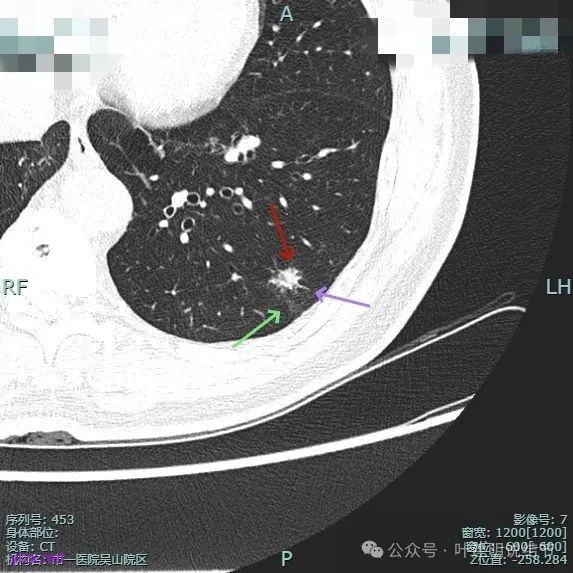

整体纵向仍偏长条些,实性部分不太致密,边上磨玻璃成分的轮廓与界限不太清楚,毛刺显得长。

仍有支气管扩张,但较2024年时密度感觉低了点。

密度较淡且缺乏收缩力。

密度杂乱,血管进入,但血管说不上明显异常增粗,磨玻璃成分淡而瘤肺界限欠清。

总体较之前密度有减低,缺乏聚拢性。

我考虑较前好转,应该是慢性炎,建议9个月后再复查。